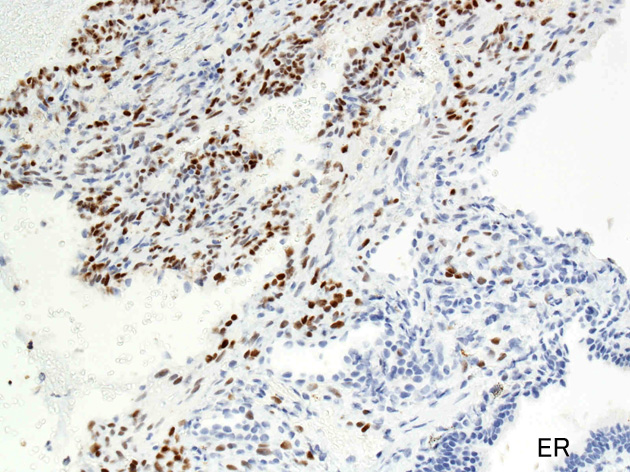

嚢胞周囲または肺血管, リンパ管, 細気管支にそうLAM cellの浸潤, 集簇を特徴とする。LAM cellには2種類が認められ, 小型紡錘形細胞と細胞質の豊富な類上皮様細胞があり, 紡錘型は主に集簇巣の中心に存在し増殖能が高い。 類上皮様LAM cellは辺縁部に多く, 増殖能は低いがHMB45を強く発現している。

LAM cellの免疫染色--SMA, desmin, vimentin(vimentinはいつも陽性とはならない)が陽性となりmuscle lineageであるが典型的な筋細胞と異なり,

免疫染色